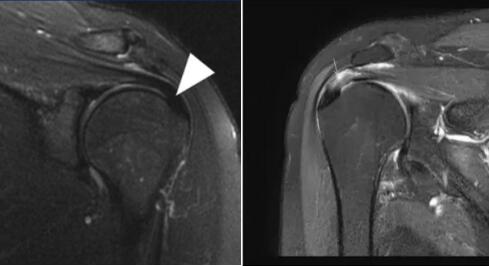

正常肩袖核磁共振圖像 ???肩峰撞擊后導(dǎo)致肩袖上表面撕裂